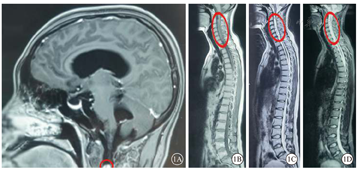

患者女,26岁。因四肢乏力伴双眼视物模糊3月余,加重2周于2021年2月8日就诊于河北大学附属医院神经外科。询问病史,2020年11月中旬,患者无明显诱因出现复视伴四肢乏力、腰部束带感,以右侧为重,未予重视;2020年12月中旬,患者因四肢乏力行走时摔倒出现右眼轻微视物模糊,但复视症状消失,于当地医院行头颅磁共振成像(MRI)检查未见明显异常,未予特殊治疗;其后右眼视力逐渐下降至眼前数指,四肢乏力进一步加重。就诊于河北大学附属医院神经外科门诊行头颅及脊椎MRI检查,提示脑积水、间质性脑水肿可能(图1A);C2~C7椎体水平硬膜下脊髓外异常信号(图1B,图1C,图1D)。神经外科以"颈椎管硬膜下髓外占位"将患者收入院。等待手术过程中,患者左眼视力急性下降至眼前数指,请眼科会诊。眼部检查:右眼视力手动/5 cm,左眼视力数指/5 cm。眼底检查,双眼视盘水肿。腰椎穿刺检查,颅内压正常,考虑与脑积水相关。眼科会诊诊断:双眼视盘水肿。建议治疗原发病。2021年2月21日,患者于全身麻醉下行椎管内占位切除(C2~C7水平段)联合椎管成形手术。手术后病理检查结果提示椎管占位-神经鞘瘤,部分区域细胞增生活跃。手术后患者肢体症状基本恢复,于2021年3月7日出院。出院时右眼视力光感,左眼视力数指/1 m。手术后25 d复查,患者双眼视力无明显改善;光相干断层扫描(OCT)检查,双眼视盘仍有水肿(图2)。